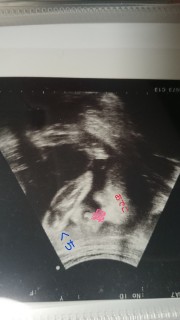

BPD 75mm FTA 53.04cm2

FL 51mm 推定体重 1470g